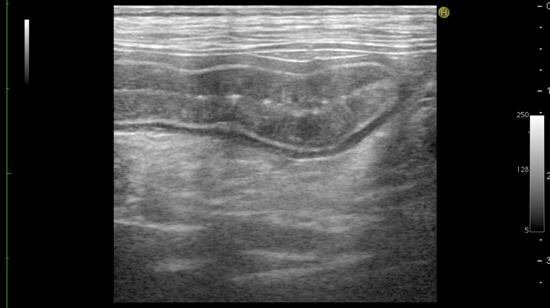

特にリンパ管拡張症は診断が見落とされがちな疾患で、超音波検査で粘膜下のリンパ管拡張の所見が得られたら腸の全層生検をおこなうことで確定診断が得られる場合があります。

超音波検査にて拡張したリンパ管を示唆する粘膜内の線状高エコー所見